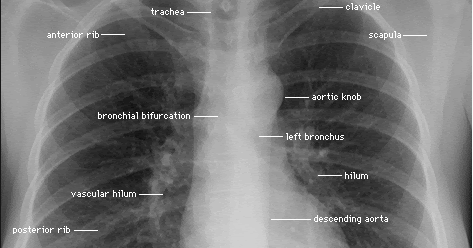

Each of these anatomical structures should be viewed using a systematic approach.

Therefore, knowing the basics and pathologies in the ed setting is very important. Published 2011 by blackwell publishing ltd. Common symptoms that can be diagnosed using chest. You have completed this module. Look for lung and pleural pathology. Many clinical conditions can be evaluated by this simple radiology test. Labeled chest radiographs teaching radiologic anatomy with a level of detail appropriate for medical students. It is almost always the first imaging study ordered to evaluate for pathologies of the thorax, although further diagnostic imaging, laboratory tests. Air spaces normally seen in. Evaluation of a chest radiograph may appear to be simple, but is in fact a complex task requiring careful observation, sound understanding of chest anatomy, and knowledge of the principles of physiology and pathology. • the straight back syndrome or pectus. Living anatomy of the chest for 1st year medical students original version compiled by dr. Each of these anatomical structures should be viewed using a systematic approach.

Major structures are shown in fig anatomy of chest. It first appears too complicated to read the chest xrays because we barely know what.